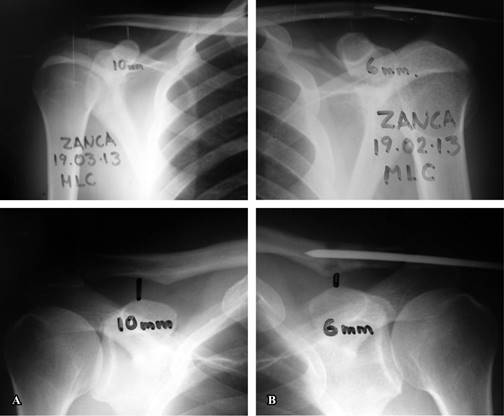

En la radiografía postoperatoria se midió, en la proyección anteroposterior de Zanca, la distancia coracoclavicular (DCC), tanto en reposo como bajo carga (con el método de Bannister) y se comparó con el lado sano (Figura 4).

Figura 4: Distancia coracoclavicular en dos casos: A) lado sano 10 mm. B) lado operado: 6 mm, sobrecorrección de 4 mm.

Los resultados se muestran en la Tabla 1. La comparación con el lado sano en proyección de Zanca dio un resultado p = 0.05039 y en la proyección de Bannister, p = 0.01775 con el método de χ2.

Radiológicamente, el aumento de la distancia coracoclavicular de 1.5 mm, en promedio, tanto en la radiografía neutra como en carga, se traduce en una pérdida de la tensión del injerto tendinoso provocando pérdida de la alineación acromioclavicular. Esta leve subluxación acromioclavicular residual, sin embargo, considerando la resección del extremo externo de la clavícula, no es significativa, pues no altera la biomecánica del complejo ligamentario del hombro al recuperarse el fulcro dado por la inserción del injerto tendinoso a la clavícula, lo que reestablece la función de los ligamentos coracoclaviculares.